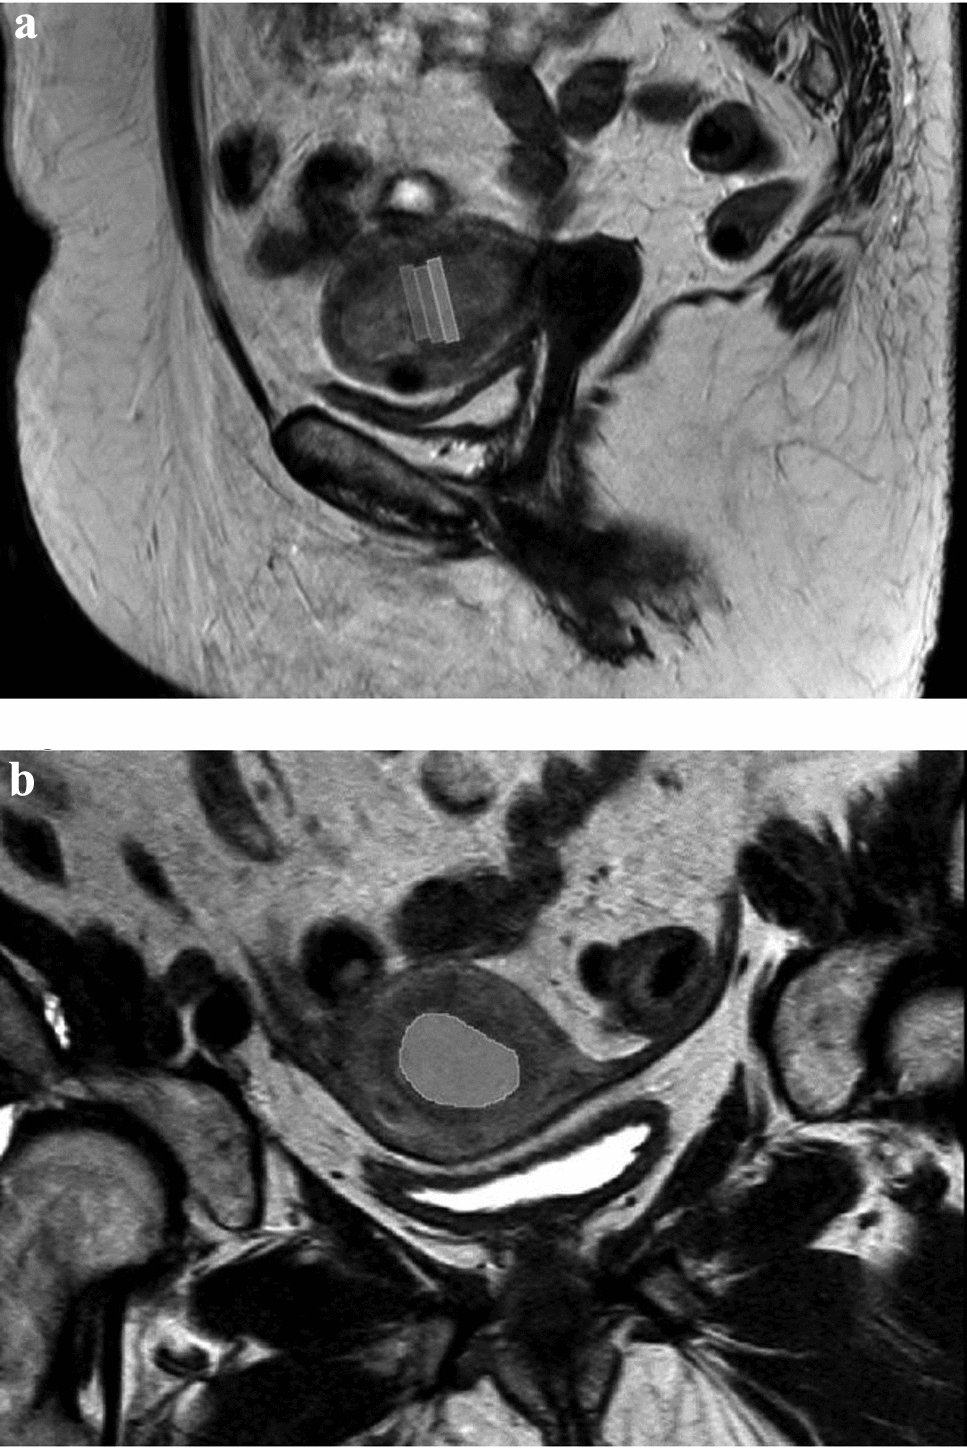

Preoperative risk assessment of endometrial cancer using histogram analysis of weighted and quantitative MRI images